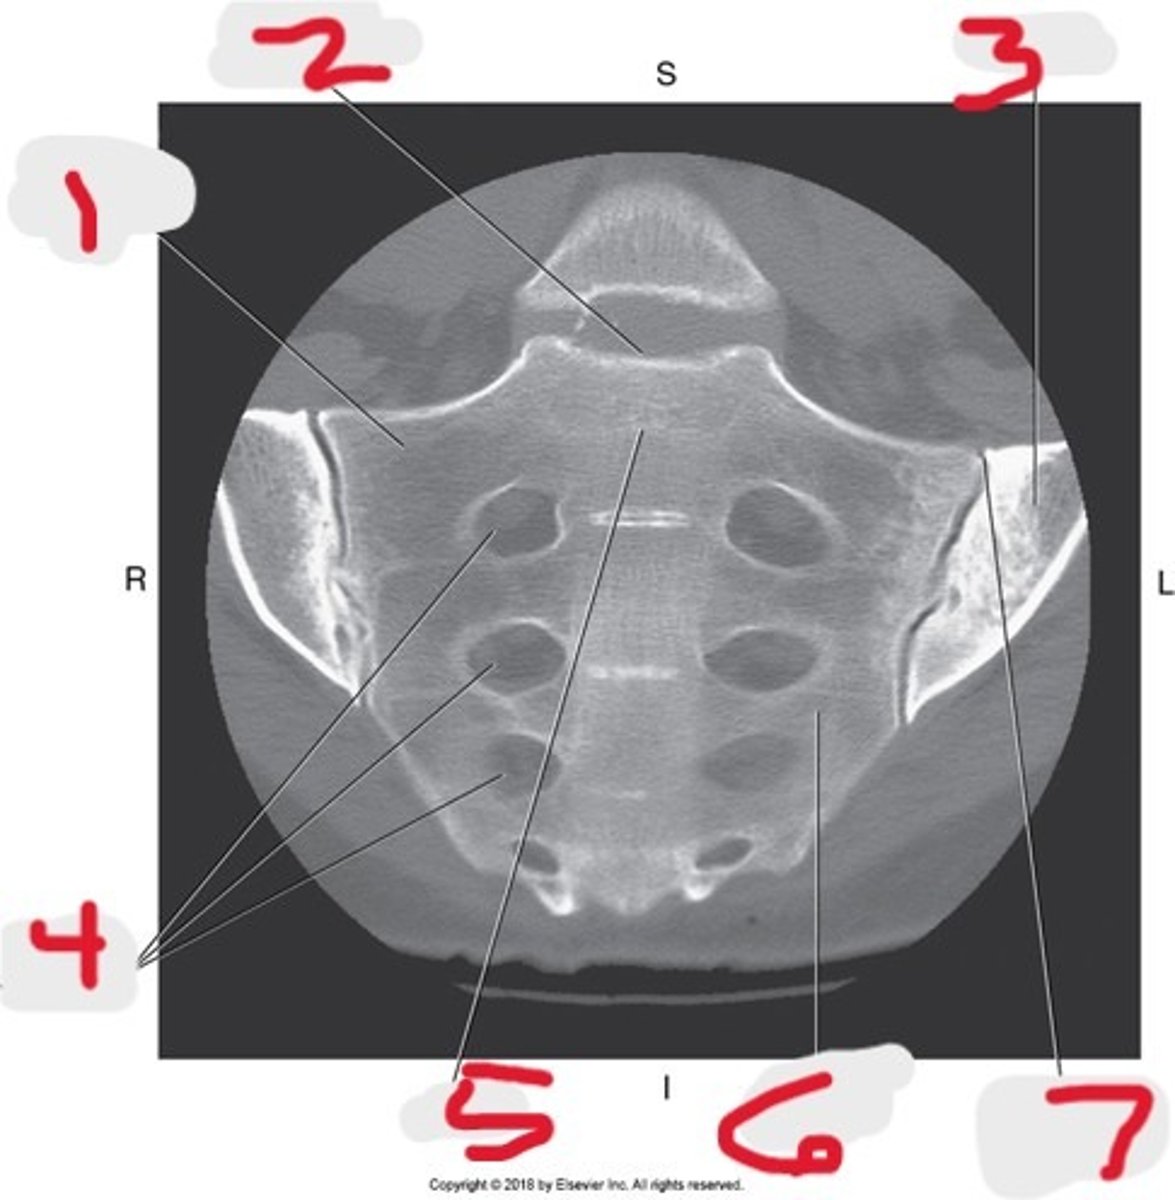

1) SI joint

2) Body

3) Sacral promontory

4) Sacral canal

5) Ilium

6) Lateral mass

7) Articular process

Name all numbered structures